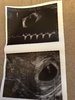

Hej, nie odzywałam się tydzień, czekałam cierpliwie na wizytę dziś. Wszystko dobrze, serduszko bije, wychodzi 6tydzien+4 dzien. Termin na 7.12 😍💞

Załączniki

• received_1102408136761656.jpeg

received_1102408136761656.jpeg

286,7 KB · Wyświetleń: 94